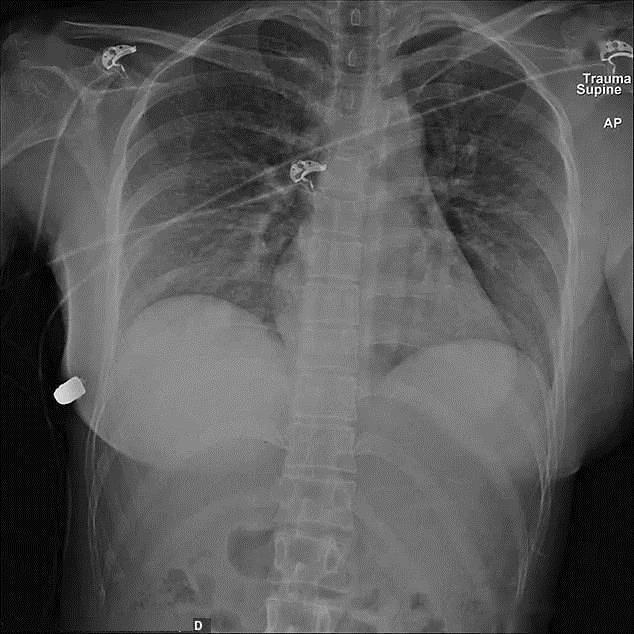

加拿大一名女子遭遇枪击时,弹头原本射入左前胸,其弹道轨迹正好伤及心肺,但她胸前的硅胶假体使弹头向右倾斜,在完全停止射击之前,再次射入右胸。最后,这颗子弹只造成了穿透性枪伤和一根肋骨骨折,而内脏却没有任何损伤,算是不幸中的万幸。

这个女人的主治医生后来向采访人员透露,她是有文献记录以来第一个被隆胸假体拯救的幸运儿,直到2020年,这份罕见的意外研究报告才在国际著名的医学学术期刊《SAGE医学》上发表,全球也只有几个地区出现类似事件。利用 X射线影像观察,医生发现假体奇迹般地使弹头以接近直角的速度高速穿越体内,而不伤及器官。伤员在手术后只移除了植入物,清洗伤口,使用了短期的抗生素就痊愈了。

【 隆胸硅胶假体还能防弹一女子枪口下幸存,医生看完一脸懵】通过X光观察,弹头几乎没有任何变形,证明硅胶没有受到很大冲击,被子弹穿过后仍能保持原来形状,再加刁钻的射击角度,提供了可以使子弹偏斜的空间,不打死人也可以说得通。距离远,动能小,或许更能解释“假胸防弹”的原因,只不过碰巧有人不幸中枪罢了。(文/山峰)